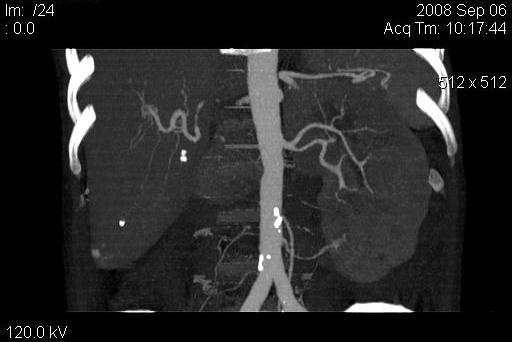

КТ Ангио почечных артерий.

Добавочные почечные артерии.

Справа добавочная артерия, питающая верхний полюс почки. Отходит от основного ствола почечной артерии. Слева дополнительная артерия, питающая нижний полюс почки, отходит от брюшной аорты, несколько выше бифуркации. В аорте видны атеросклеротические бляшки, одна из них довольно близко к устью добавочной артерии. Это может иметь клиническое значение.